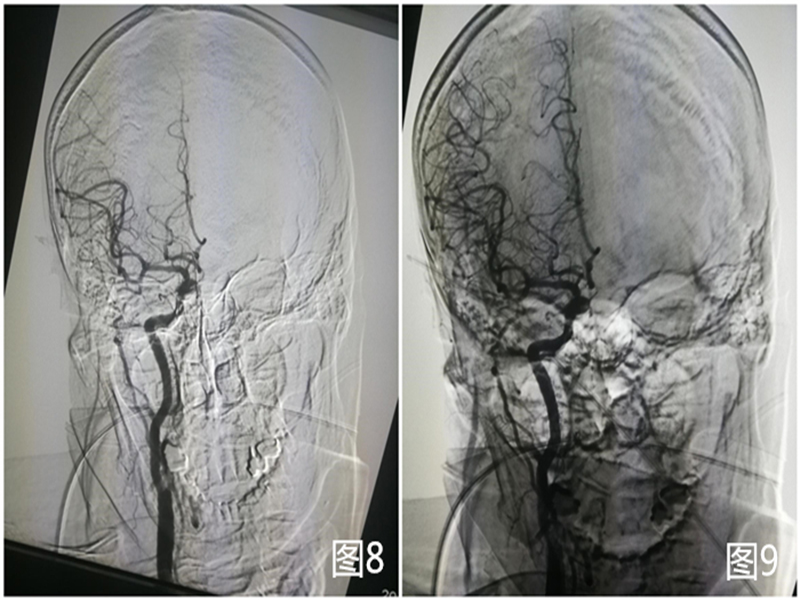

8 9 )